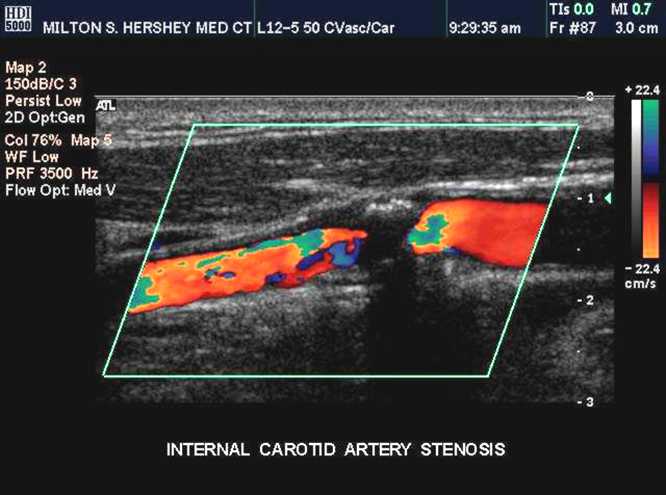

到了病区照常问病史查体。在检查颈部时,听到颈动脉有明显的血管性杂音。有杂音,提示颈动脉有病变,进一步颈动脉超声检查,发现双侧颈动脉都是90%以上的狭窄,动脉粥样硬化病变几乎堵死了血管。

检查颈动脉,身体检查可以听诊颈部血管有没有杂音(轻度的狭窄不一定有杂音),辅诊检查初筛是颈动脉超声,无创伤,可以重复,但一般对狭窄病变有些放大(就是说看起来可能比真实的狭窄要严重些);进一步检查可以做颈部血管的磁共振血管造影或者CT颈动脉造影,这两种检查也属于无创,但是需要注射造影剂的;再就是直接插入导管做颈动脉造影。